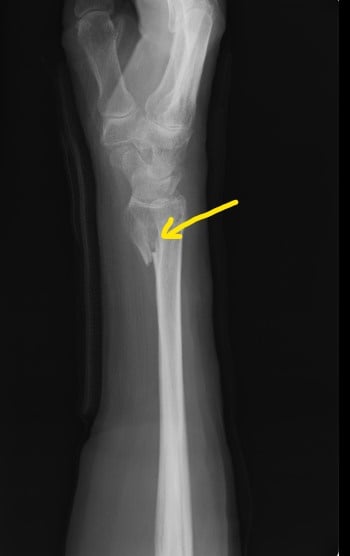

〇前腕骨遠位端骨折

当症例も手術の日程が決まっていましたがインターネットで当院を知り遠くから相談に来らました。

レントゲンとCTを見させてもらいましたが、骨折に伴い第三骨片がはみ出しています。

患者さんンは全身麻酔に抵抗があり、どうしても避けたいとのことでした。

当院で治療するとなると、当初は毎日来院していただき固定を

確認 血行障害を防ぎ 患部の清拭 超音波治療 動かせる指の

運動療法を行います。

ご住所をお聞きしたところに私の信頼する先生のご近所だったので、保存療法を希望している旨をお伝えして経過観察をお願いしました。

2か月経過したころ当院に戻られ今後のマッサージ リハビリを希望されました。

手術はしませんでしたが経過は良好です。